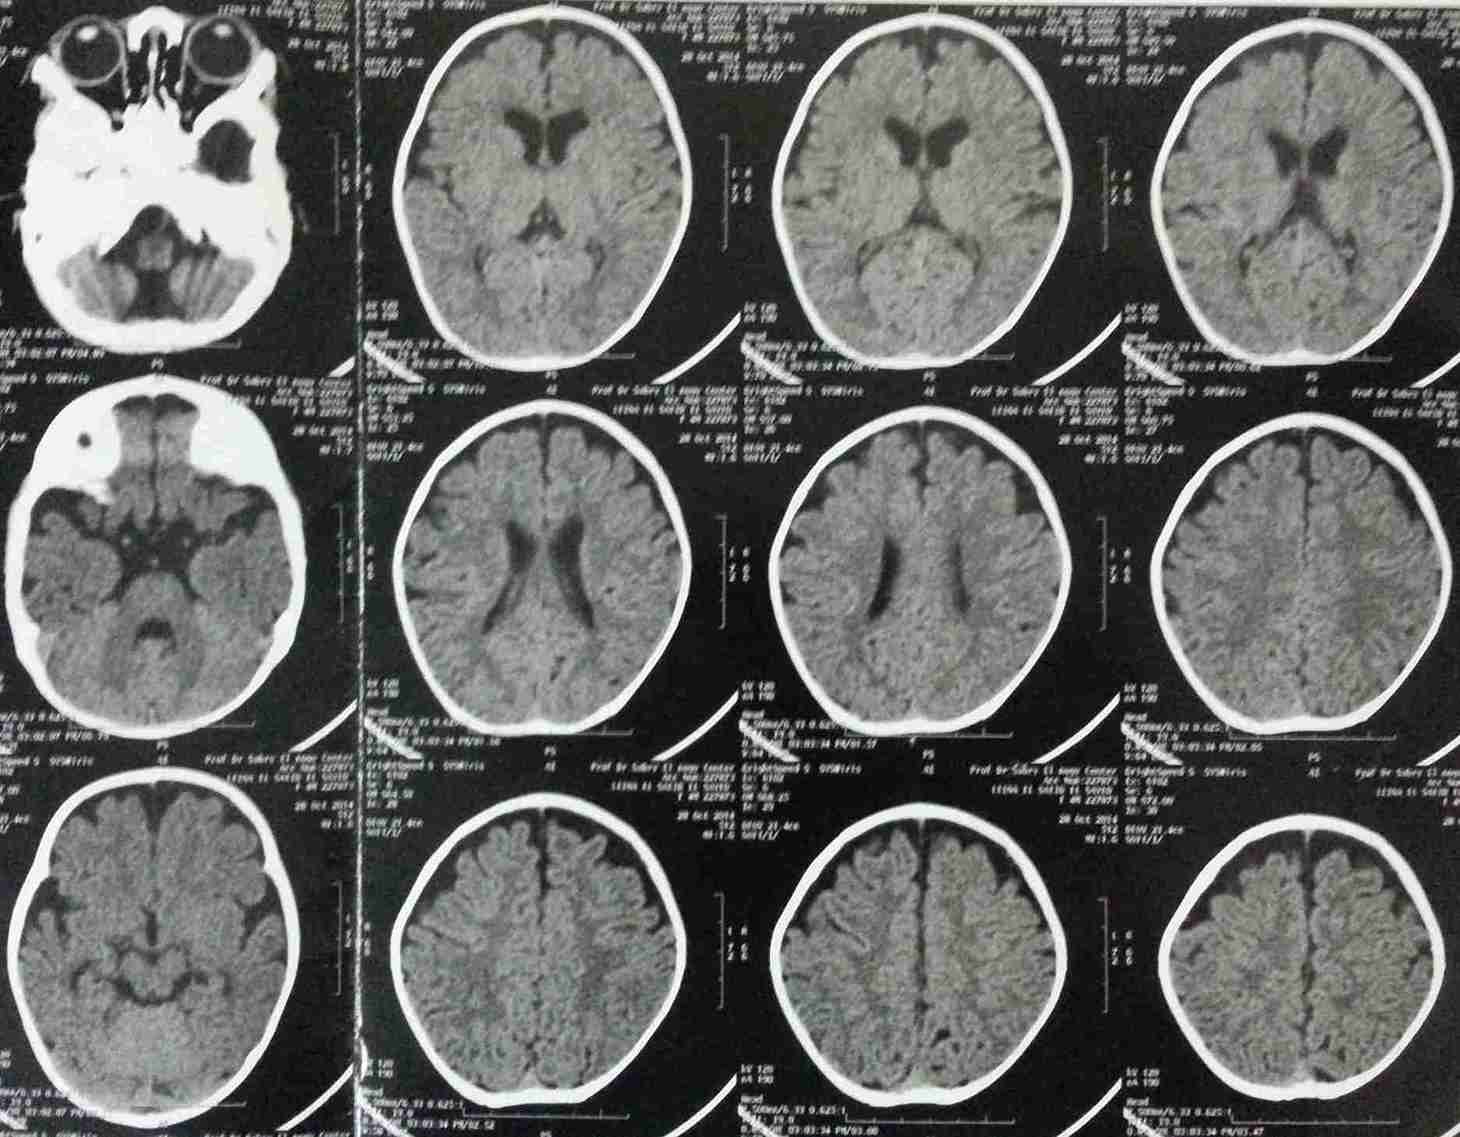

طفلة اربع شهور محولة من استشاري الاطفال بسبب البكاء المستمر الغير مبرر المصحوب بنوبات قئ وبعد توقيع الكشف لوحظ تفلطح او قصر الجبهه وبعمل اشعة ثلاثية الابعاد ومقطعية علي المخ وجد بها انسداد مبكر للدروز الاكليلية الجبهية بالجهتين اليمني واليسري مع انغلاق جزئى لليافوخ الامامي. وتم اجراء جراحة لتفتيح الدروز المنغلقة ثم متابعة الطفلة حتي اخر زيارة وهي بنت اربع اعوام بحالة ذهنية ممتازة.